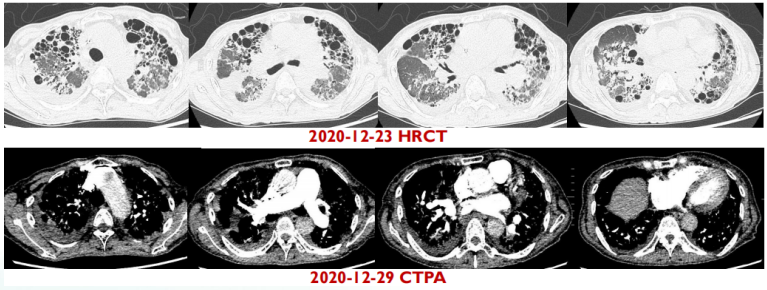

高分辨率CT(HRCT)和CT肺动脉造影(CTPA)检查如图7所示。

图片

7  患者术前HRCT和CTPA检查